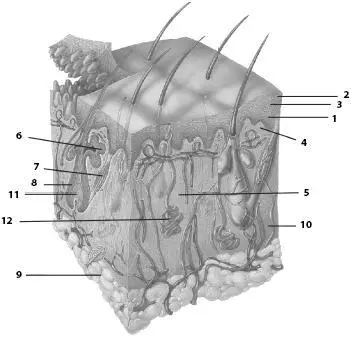

Кожа состоит из эпидермиса и дермы ( рис. 77 ). Эпидермис – это многослойный плоский ороговевающий эпителий, толщина которого зависит от выполняемой функции. Так, на участках, подвергающихся постоянному механическому давлению, его толщина достигает 0,5–2,3мм (например, подошвы). На груди, животе, бедре, плече, предплечье, шее и т. д. толщина его не превышает 0,02–0,05 мм.

Рис. 77. Строение кожи.1 – эпидермис, 2 – роговой слой, 3 – базальный слой, 4 – сосочковый слой, 5 – сальная железа, 6 – соединительнотканные волокна (коллагеновые, эластические, ретикулярные) и клетки, 7 – пучки миоцитов, 8 – волосяная луковица, 9 – дольки жирной ткани, 10 – сетчатый слой, 11 – корень волоска, 12 – потовая железа

Дерма, или собственно кожа , толщиной 1–2,5 мм образована соединительной тканью. В ней различают сосочковый и сетчатый слои. Сосочковый слой находится под базальной мембраной эпидермиса, он сформирован рыхлой волокнистой неоформленной соединительной тканью, которая расположена в виде сосочков, внедряющихся в эпидермис. Будучи богато снабженным кровеносными сосудами, сосочковый слой осуществляет питание эпидермиса, который лишен сосудов. В сосочковом слое имеются гладкие мышечные клетки. Благодаря наличию сосочков на поверхности кожи видны гребешки , разделенные бороздками кожи . Сложное переплетение гребешков и бороздок образует рисунок, индивидуальный для каждого человека и не меняющийся в течение всей жизни.

Сетчатый слой состоит из плотной неоформленной соединительной ткани. В сетчатом слое залегают корни волос, потовые и сальные железы.

Пучки коллагеновых волокон проходят в подкожную основу, содержащую жировую ткань. Этот слой играет важную роль в терморегуляции и является жировым депо организма. Волосы сменяются в сроки от 2–3 месяцев до 2–3 лет.

Волосыявляются производными эпидермиса. Почти вся кожа покрыта волосами. Исключение составляют ладони, подошвы, переходная часть губ, головка мужского полового члена и малых половых губ женщины. Наибольшее число волос обычно на голове. Характер оволосения зависит от пола, возраста и относится к вторичным половым признакам. Волос имеет выступающий над поверхностью кожи стержень и корень, лежащий в толще кожи. Длина стержня колеблется в пределах от 1–2 мм до 1,5 м, а толщина – от 0,005 до 0,6 мм.

Стержень волоса состоит из мозгового и коркового вещества, преобладает последнее. Корковое вещество образовано плоскими роговыми чешуйками, заполненными в основном кератином. Кроме того, в них содержатся зерна пигмента и пузырьки воздуха. Клетки мозгового вещества лежат друг на друге, они богаты трихогиалином, который превращается в каратин, а также содержат пузырьки воздуха и зерна пигмента. С возрастом количество пузырьков воздуха увеличивается, а синтез пигмента постепенно прекращается, волосы седеют. Корень волоса расположен в волосяном фолликуле , образованном эпителиальным фолликулом и соединительнотканной сумкой волоса. К сумке прикрепляется гладкая мышца, поднимающая волос . Лишь волосы, расположенные на подбородке и в области лобка, лишены этой мышцы. В сумку открывается сальная железа. Сокращаясь, мышца поднимает волос, сдавливает сальную железу, благодаря чему выделяется ее секрет.

Корень переходит в расширенную волосяную луковицу , в которую впячивается сосочек волоса, богатый кровеносными капиллярами. Над сосочком расположен матрикс, который представляет собой ростковую часть волоса. За счет деления клеток, которые передвигаются вверх, волос растет. Между эпителиальными клетками матрикса залегают пигментные пятна, синтезирующие пигмент меланин. Как и в клетках эпидермиса, зерна меланина захватываются эпителиальными клетками, в которых по мере их ороговения меланин входит в состав кератина, тем самым окрашивая волос. Сосуды сосочка волоса питают луковицу.